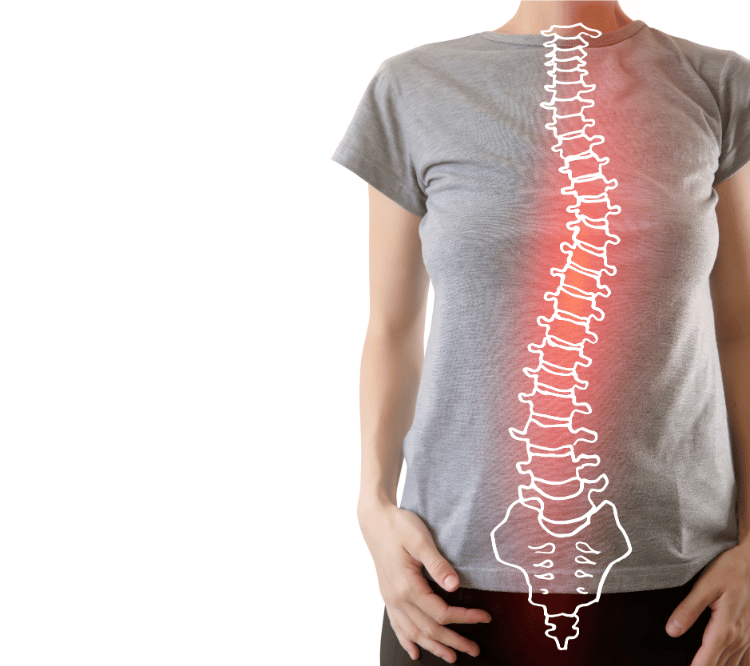

- Hrbtenica

Kaj je išias in 4 uporabni nasveti za odpravo

Išias ali ishiadične bolečine so verjetno najbolj znane bolečine, ki...

Kako za vedno odpraviti bolečine v križu

V tem članku bomo razbili najpogostejše mite o bolečinah v...Izpostavljeno